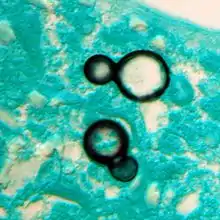

Large, broadly-based budding yeast cells characteristic of Blastomyces dermatitidis in a GMS-stained biopsy section from a human leg.